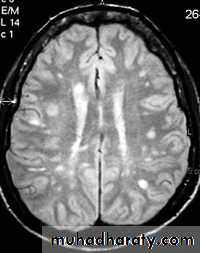

- the most characteristic appearance is that of peri ventricular nodular Hyper intense lesions on T2 weighted images.

-the plaques are also well seen at the gray- white matter interfaces.

-MRI can even image lesions in the spinal cord , brainstem & cerebellum.

-some lesion may show a central area of greater signal intensity , resembling a target.

-contrast enhancement after giving gadolinium occurs in the acute phase indicating activity & in the chronic phase doesn't enhance.

SAGITAL FLUID ATTENUATION INVERSION RECOVERY SEQUENCE: OVOID PLAQUES ( HIGH SIGNAL INTENSITY) , WHICH ARE PERPENDICULAR TO LATERAL VENTRICLE.